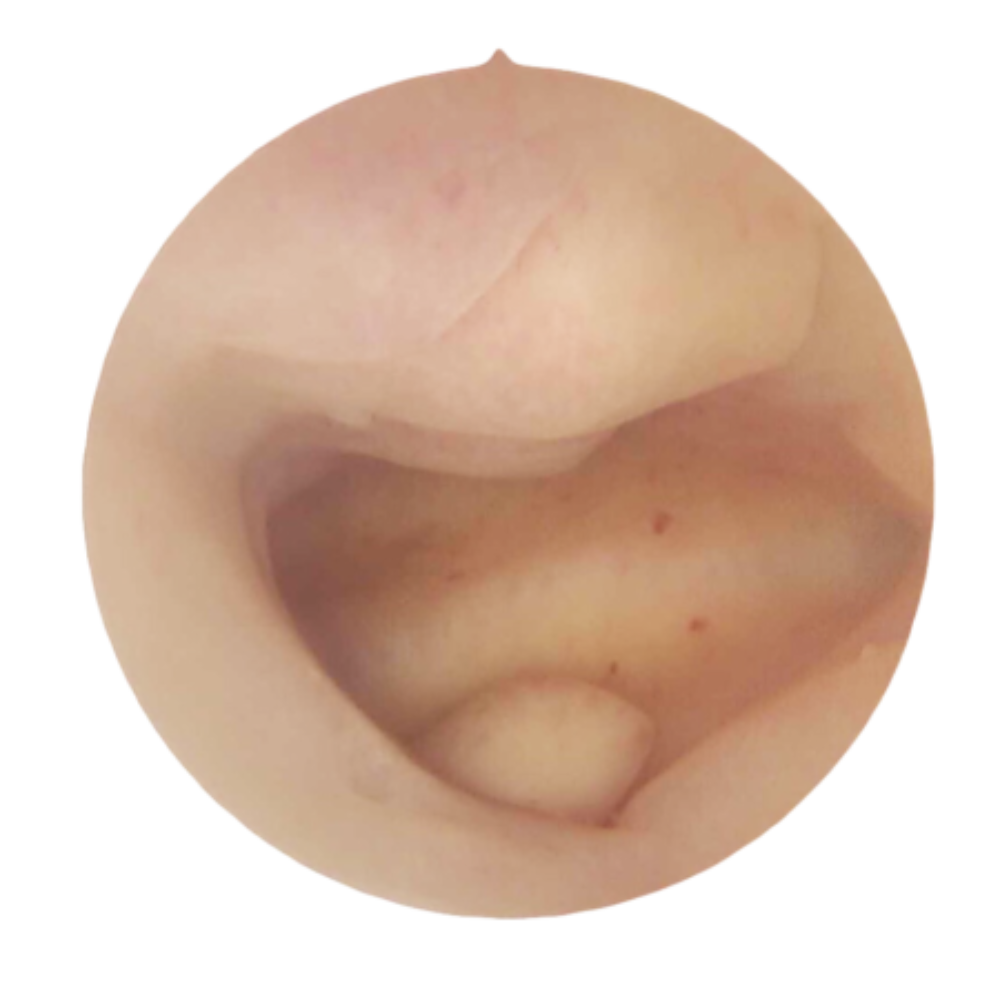

MiniCare

L’alliance parfaite entre préservation et performance